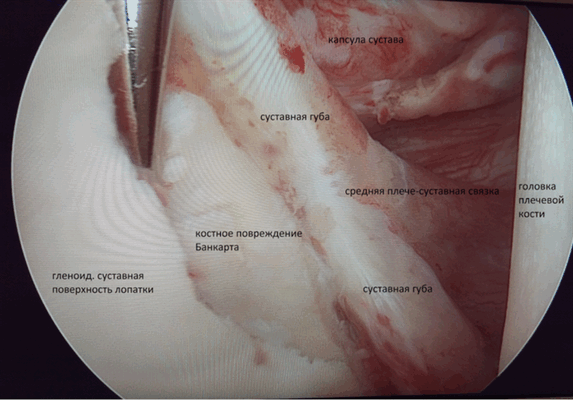

- повреждение Банкарта — разрыв происходит в передней части хряща. Чаще возникает одновременно с вывихом плечевой кости. Бывает классический — полный отрыв суставной губы от впадины лопатки и крайний — разрыв сочетается с переломом кости. По степени повреждения классифицируют на полный и неполный разрыв;

- Нестабильное состояние плечевого сустава(повреждение Банкарта, вывих плеча, в том числе и первичный)

А) При переднем вывихе ПС вмешательство направлено на восстановление суставной губы (операция Банкарта). Метод нацелен на восстановление целостности суставной губы при помощи фиксации оторванной части на край суставного отростка лопатки.

Б) При привычном заднем вывихе суставная губа восстанавливается вместе с ушиванием капсулы сустава сзади. В исследовании G.W. Misamore et W.A. Facibene показано, что после артроскопии 13 из 14 спортсменов, прооперированных таким методом, смогли достичь своих прежних физических кондиций и результатов.

В) В случае сочетания заднего повреждения Банкарта, сопровождающегося задним разрывом связки суставной впадины лопатки, артроскопия позволяет зафиксировать оторванную суставную губу к краю суставной впадины лопатки, заднюю часть капсулы плеча к задней части головки плеча. В качестве фиксатора используются биорассасывающие фиксаторы-якоря.